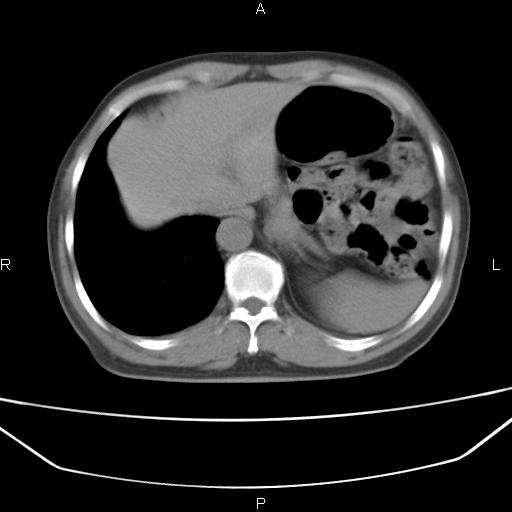

患者,男。50岁。近几日有咳嗽症状,无其他不适,既往病史无,考虑膈疝。请前辈们看看指导指导。

膈膨升,左下肺通气不良,膈肌好像还完整。

考虑左侧膈疝。

左侧膈疝。

符合隔膨升,膈肌较完整。